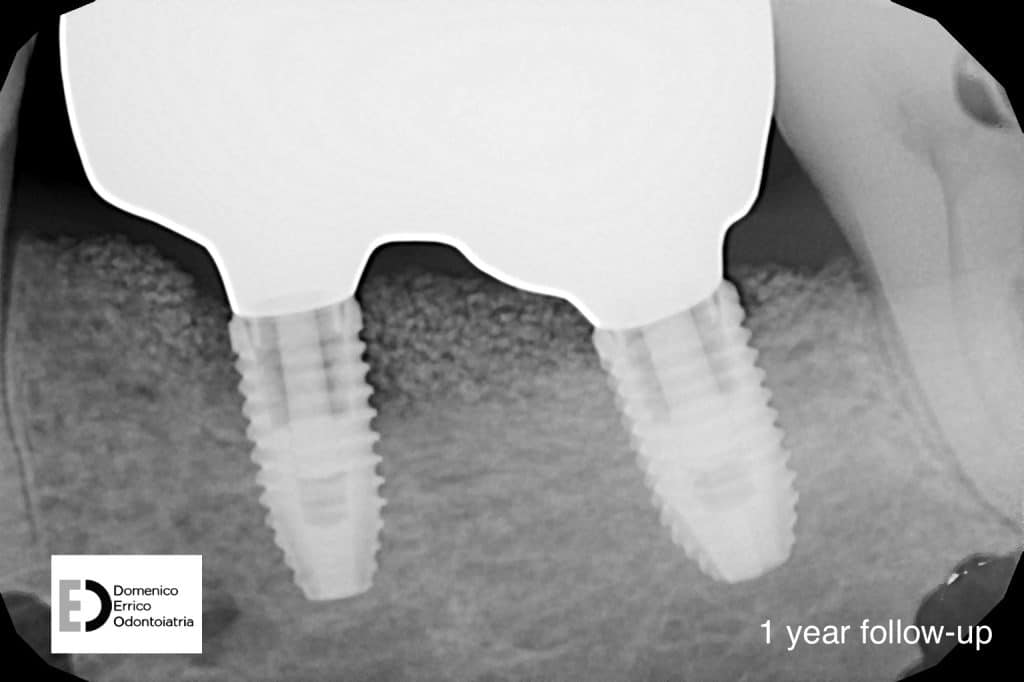

After 4 months we can appreciate the perfect tissues healing, the bone level stability, a perfect implants osteointegration, with a complete recovery of masticatory function and an aesthetic balance between teeth and gum portions.